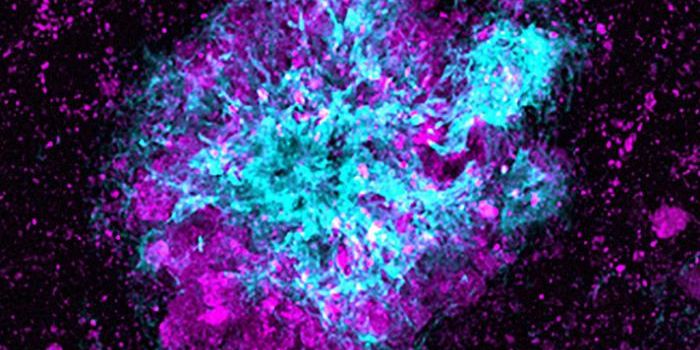

MAR 08, 2016ImmunologyScientists have grown tiny, barely visible “mini-brains.” These balls of neurons and other human cells mimic ...